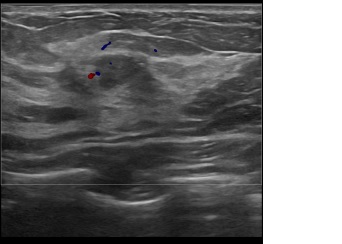

상기환자는 양성추정결절 추적관찰하시는 40대 중반

여성분으로 의심스러운 우측혹 조직검사 시행해 유방암 진단되었습니다.